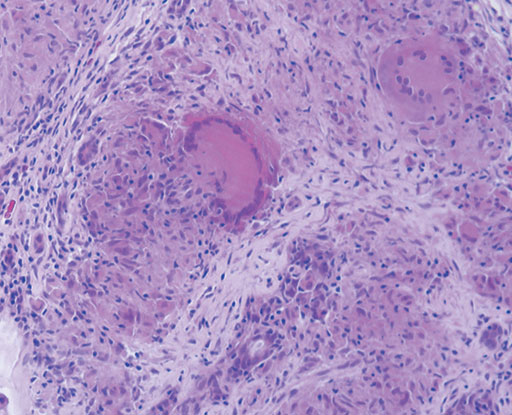

Sarcoidosisは通常,縦隔および両側肺門部の腫大をともなって発症するが,まれに皮膚,中枢神経,軟部腫瘍で発症することがある.腎病変は,高カルシウム血症にともなう腎結石や腎障害がみられるのが一般的であるが,まれに多発性のnoduleを形成することが知られている.腎臓の多発性結節の鑑別としては,von Hippel-Lindau病に認められる腎癌,転移性腎腫瘍,悪性リンパ腫,結核等の感染症,腎盂腎炎が鑑別に上がる.今回の症例では筋肉内に比較的,均一に造影される結節が認められることからsarcoidosisの診断が示唆される.転移性腫瘍は通常,内部に壊死を伴って不均一に造影される.悪性リンパ腫ではdiffuseな筋肉の腫大を呈することが多い.Sarcoidosisの筋病変は単発性または多発性の結節を呈するnodular typeとmyopathic typeが知られている.結節型はMRIでは,T1強調像,T2強調像,造影T1強調像のいずれのsequenceにおいても中心部に不規則な星ぼう状の低信号(dark star sign)を呈するのが特徴的である.Myopathic typeではMRIでは異常信号として捉えにくいが,67Gaシンチでは筋肉に沿って瀰漫性の集積が認められる.実際の症例では皮膚,腎臓,筋肉いずれの病変からもbiopsyによりsarcoidosisの診断が得られている.腎臓の病理では系球体周囲に非乾酪性肉芽腫の形成を認め,また一部に巨細胞も認める.

• 図3 HE染色(×200)